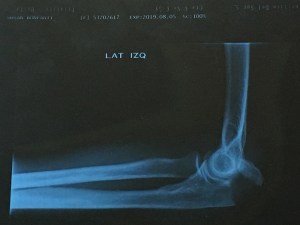

But then, not so yay for fracturing my elbow …

Yes, that piece of bone pointing to the bottom right really shouldn’t be there. It belongs to the long bone at the bottom of the x-ray. Anyway, it could have been worse. It was my left arm and I’m right-handed. It was a simple fracture. But …